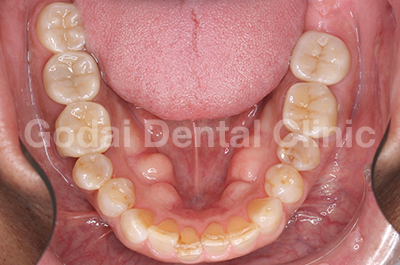

患者様は20代女性、むし歯の治療と歯並びを改善したいという主訴で来院されました。口の中を診査していくと、奥歯に装着された古い金属の下がむし歯になっていました。また下の前歯がガタガタになってきていること、前歯が出てきたことを患者様は気にしていました。むし歯については、審美性・耐久性・生体親和性を考えセラミックス治療を行い、歯並びの改善はマウスピースを用いたインビザライン矯正治療を行うことになりました。

まずはセラミックスを用いてむし歯の治療を行いました。その後、インビザライン矯正治療に移行し、約1年の移動期間で治療を終えることができました。金属を外しセラミックスで治療したことで口の中が明るくなり、矯正治療により上の前歯が出ていることと下の前歯のガタガタを改善することができました。歯並びが良くなることで将来的にむし歯と歯周病のリスクを下げることができますし、ステインも付着しにくくなるので今後のメンテナンスをやりやすくなるのが大きな魅力です。

治療前1

治療後1

治療前2

治療後2

治療前3

治療後3

治療前4

治療後4